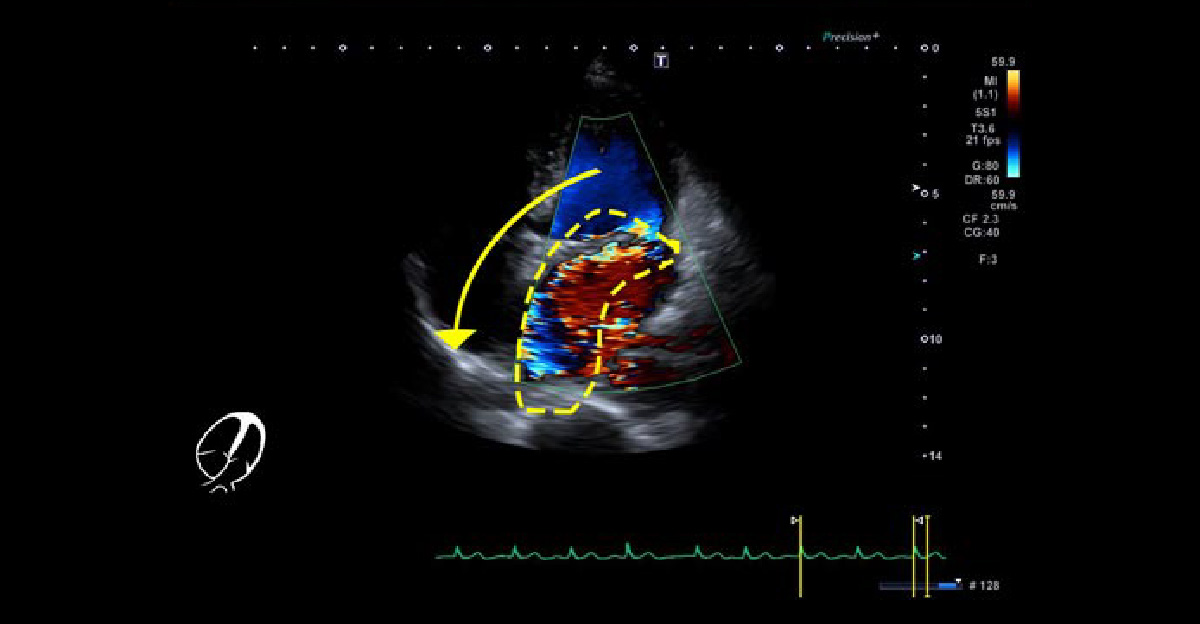

僧帽弁閉鎖不全症 その① 僧帽弁逸脱症

若年でも手術に至ることが多く、心雑音がある患者さんは注意が必要です。

僧帽弁逸脱症

心エコー4腔像 心4腔像で、偏った逆流ジェットが特徴です。